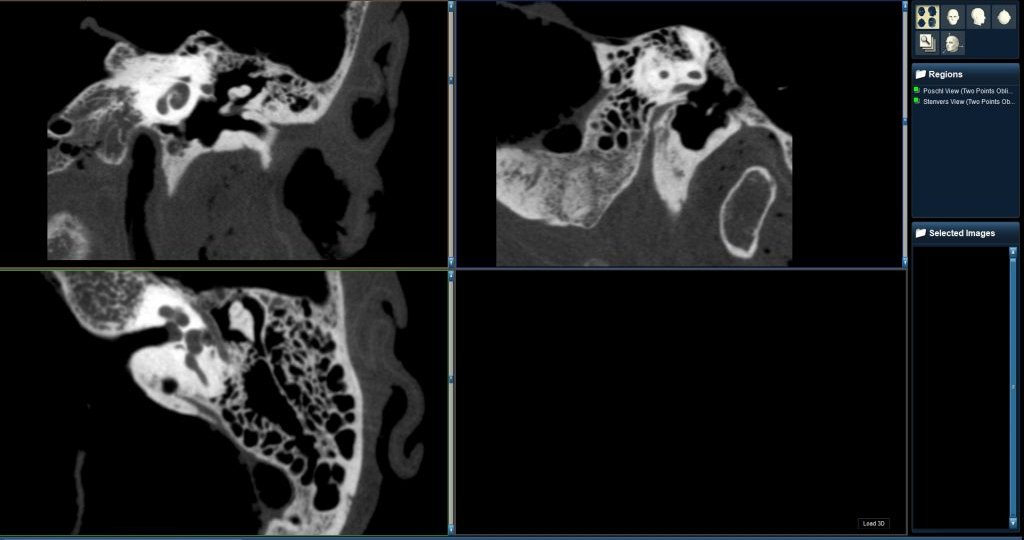

A team of surgeons used Xoran’s new xCAT XL for a cochlear implant surgery, repairing A RARE congenital malformation of…